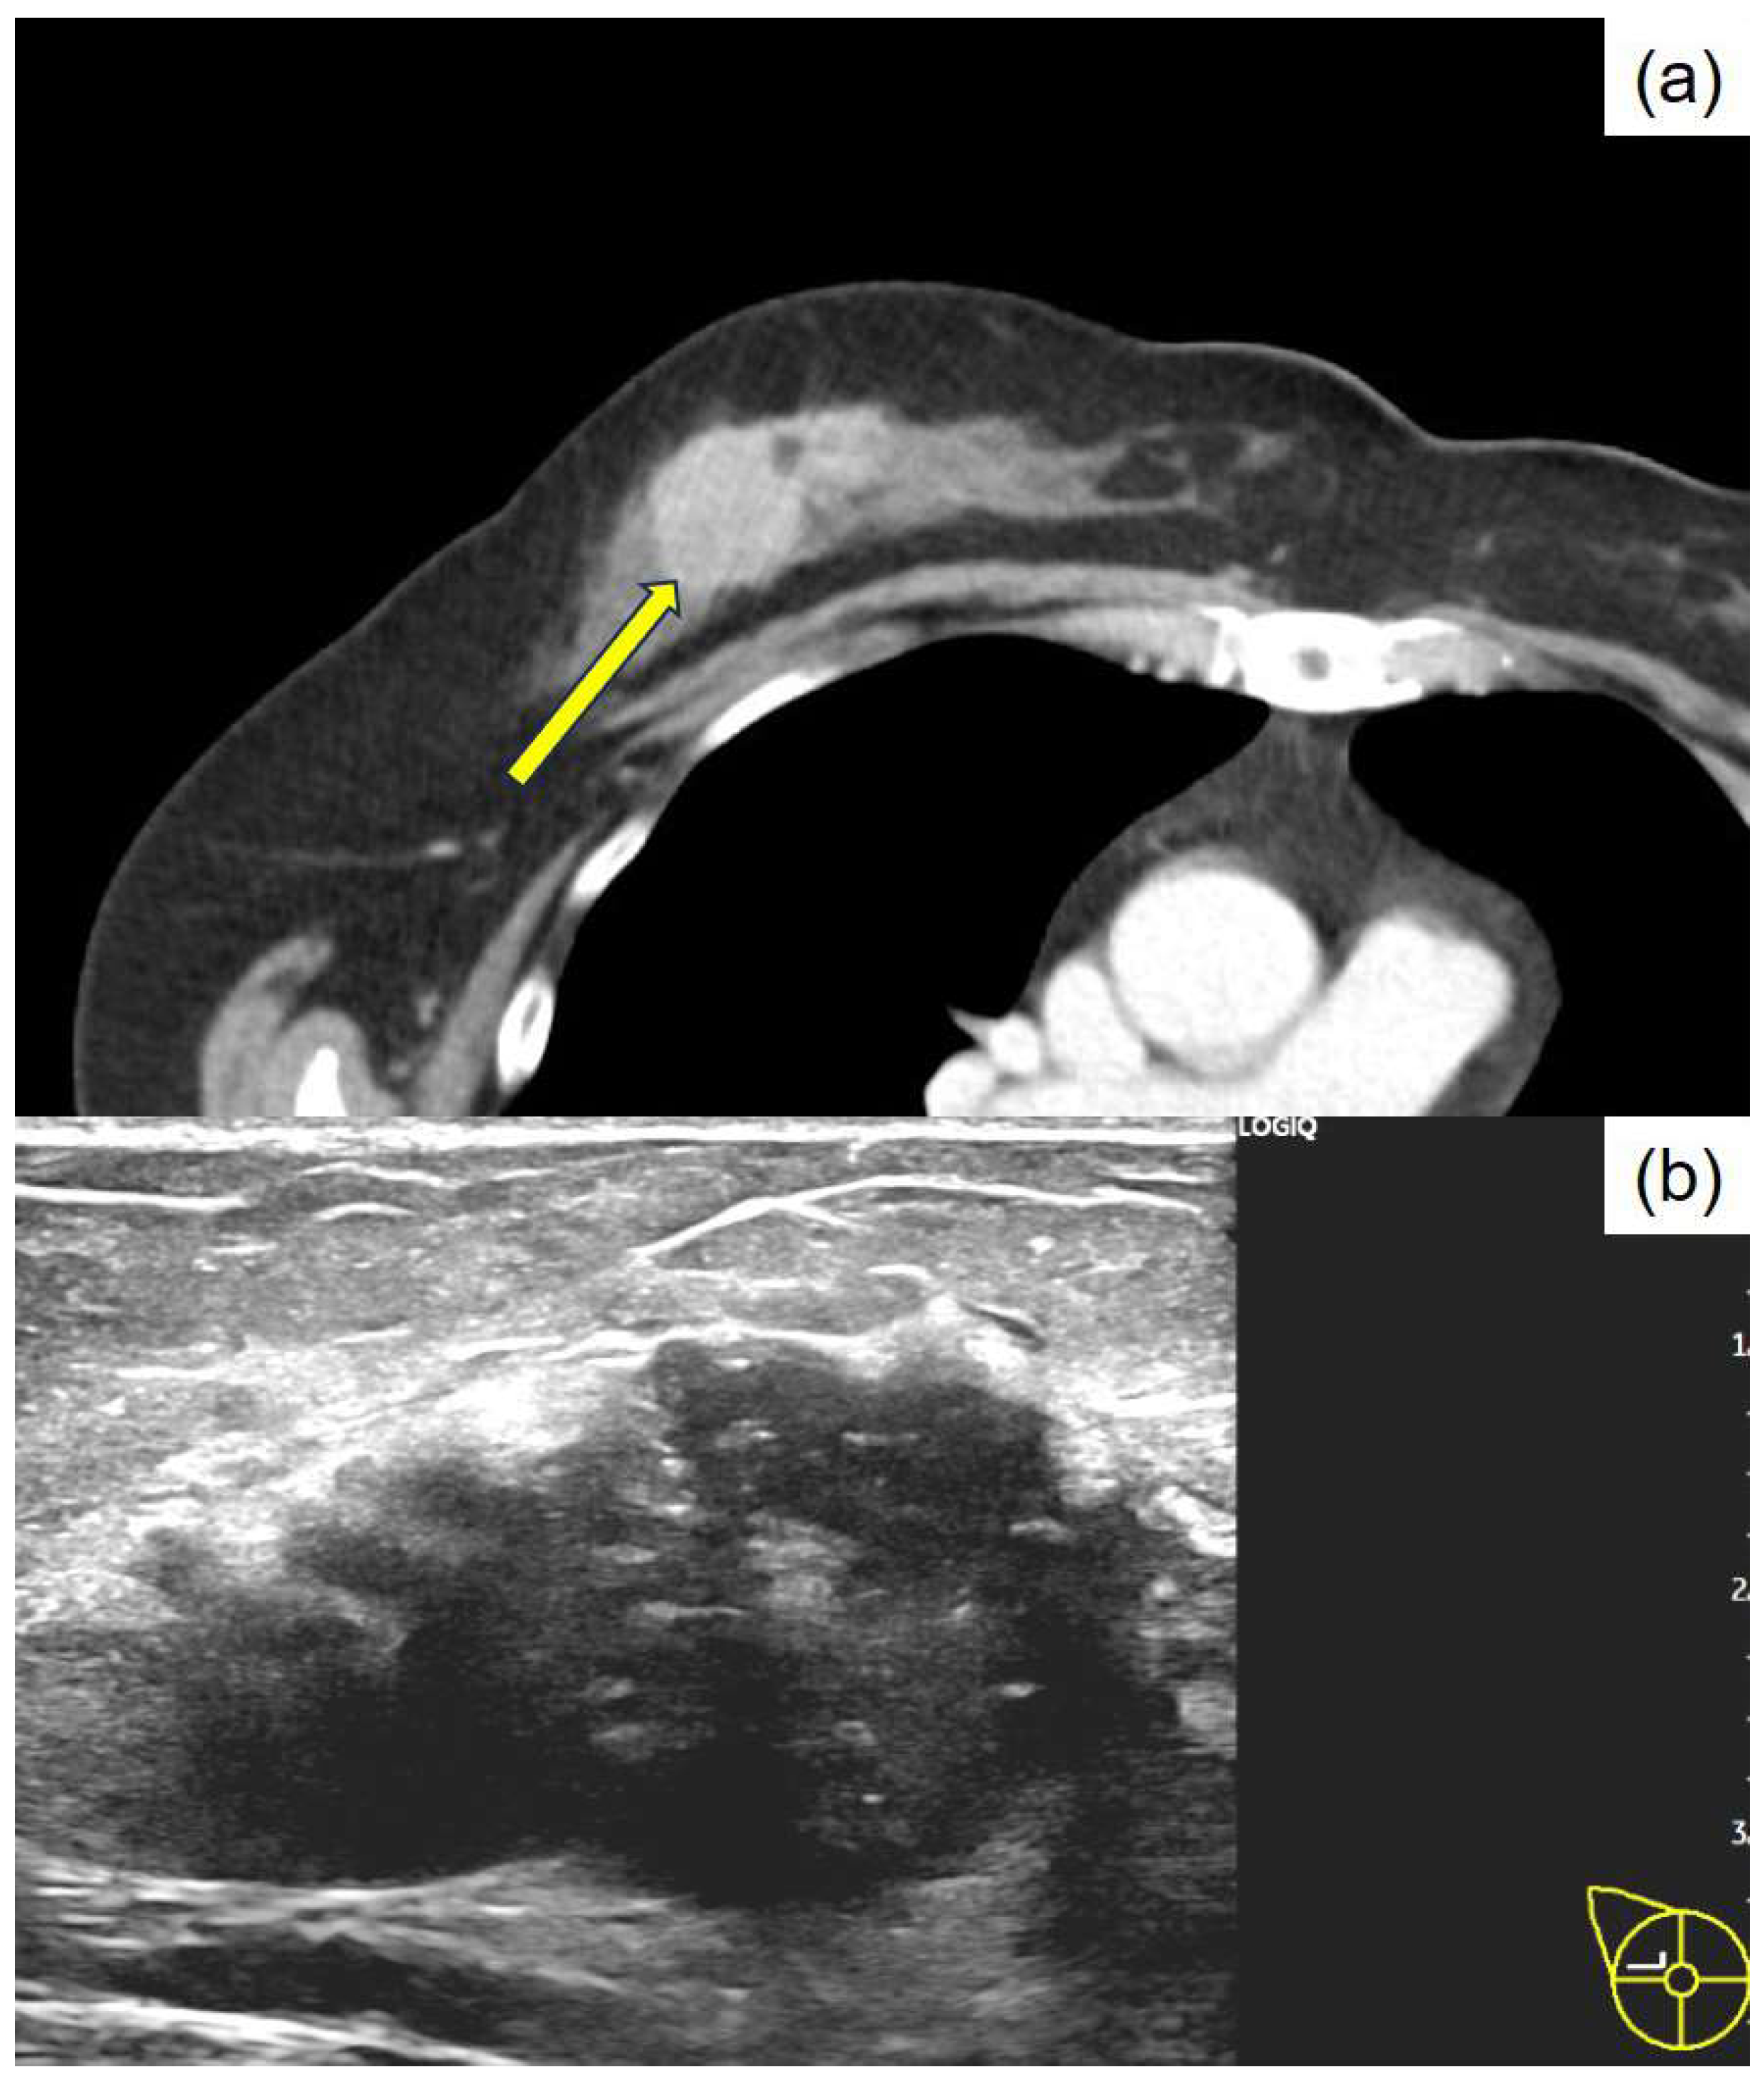

Apocrine Breast Carcinoma with Thanatosomes (Hyaline Globules)

Tachibana, M.; Nozawa, M.; Isono, T.; Tsukamoto, K.; Kamimura, K. Apocrine Breast Carcinoma with Thanatosomes (Hyaline Globules). Diagnostics 2025, 15, 1768. https://doi.org/10.3390/diagnostics15141768